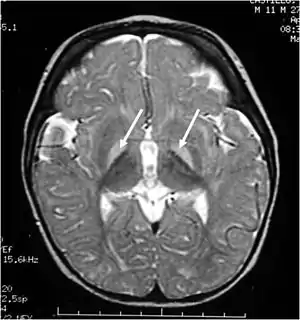

Brain MRI. Hyperintense basal ganglia lesions on T2-weighted images.

These impairments are associated with lesions in the basal ganglia, auditory nuclei of the brain stem, and oculomotor nuclei of the brain stem. Cortex and white matter are subtly involved. Cerebellum may be involved. Severe cortical involvement is uncommon.